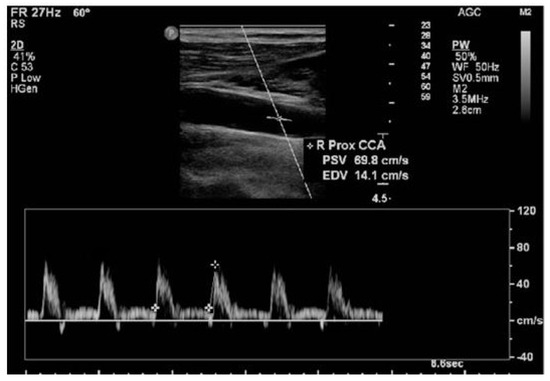

2.2. Procedures